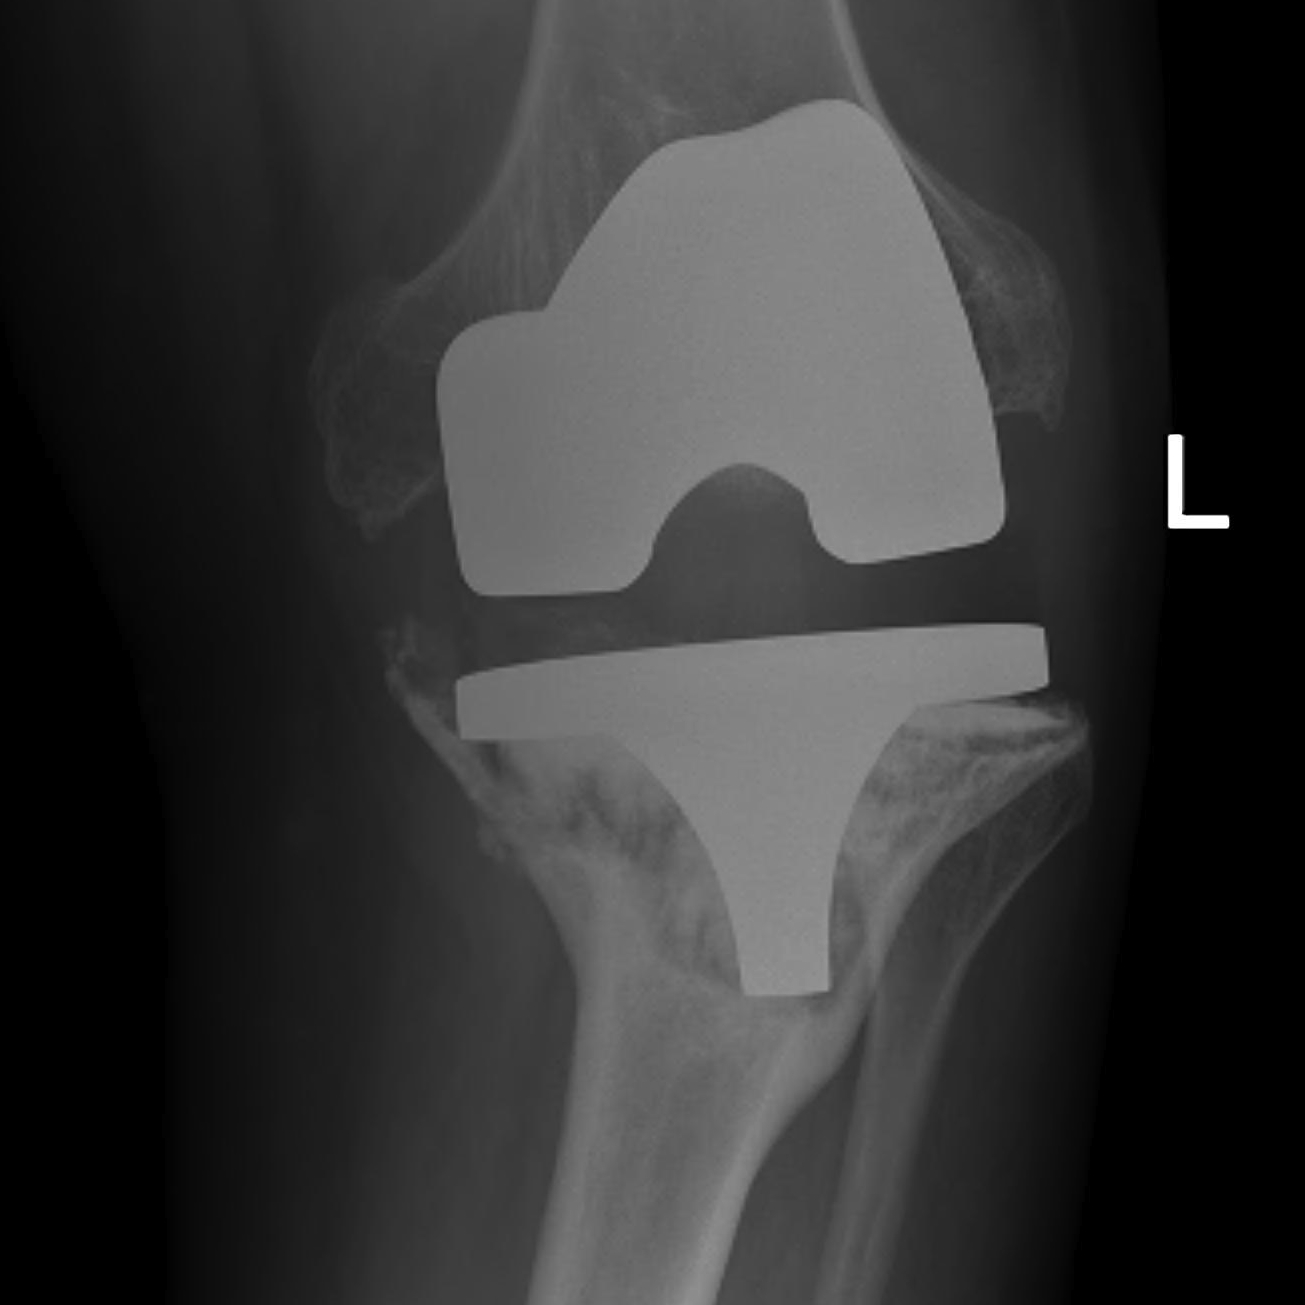

Prepare Tibia

Insert trial intramedullary stem

Find IM canal

- ream until appropriate diameter

- desired length

- place trial

- set proximal cutting jigs off IM stem

Proximal tibial cut

Minimal tibial cut

- cut 1 - 2 mm off high side to preserve bone

- usually lateral side

- make resection for desired augment (5 or 10 mm) other condyle

- use jig

Insert trial tibia

Use offset as required

- ensures tibial component good fit on tibia

- tibial component not dependent on stem position

- ensure not internally rotated

- attach required augments